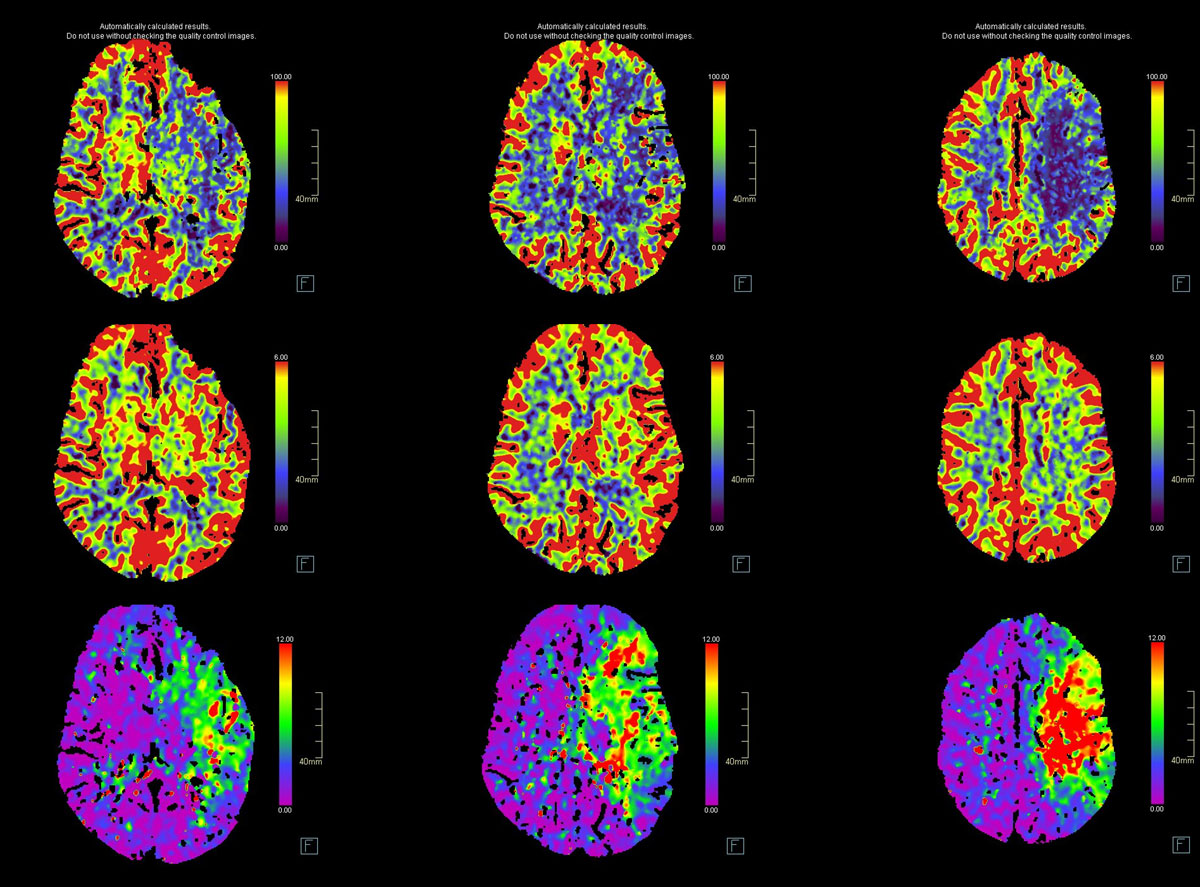

CT – CTA - CTP

24h CTA and CTP